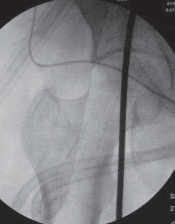

TECHNIQUES

4. Using fluoroscopy, the alignment rod is placed at the center of the femoral head (

TECH FIG 3A

) and then at the center of the ankle joint (

TECH FIG 3B

).

D E TECH FIG 3•A.

Fluoroscopic image of alignment rod through femoral head.

B.

Fluoroscopic image of the alignment rod in the center of the ankle.

C.

The subsequent location of the alignment rod in the knee. This initial mechanical axis must be corrected. It should match with the preoperative planning.